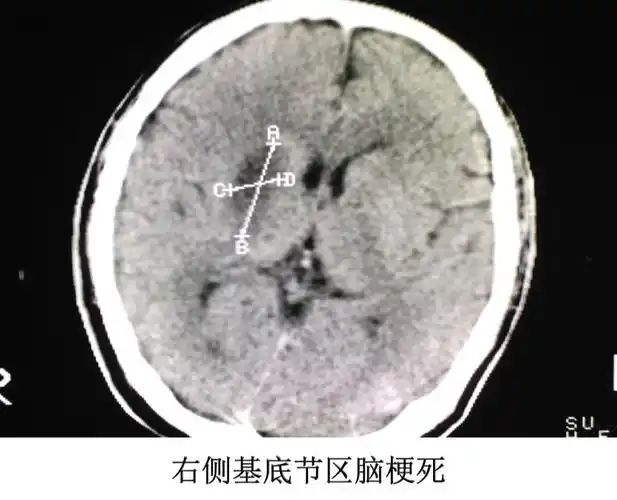

读懂头颅ct并不难教你成为读片小能手